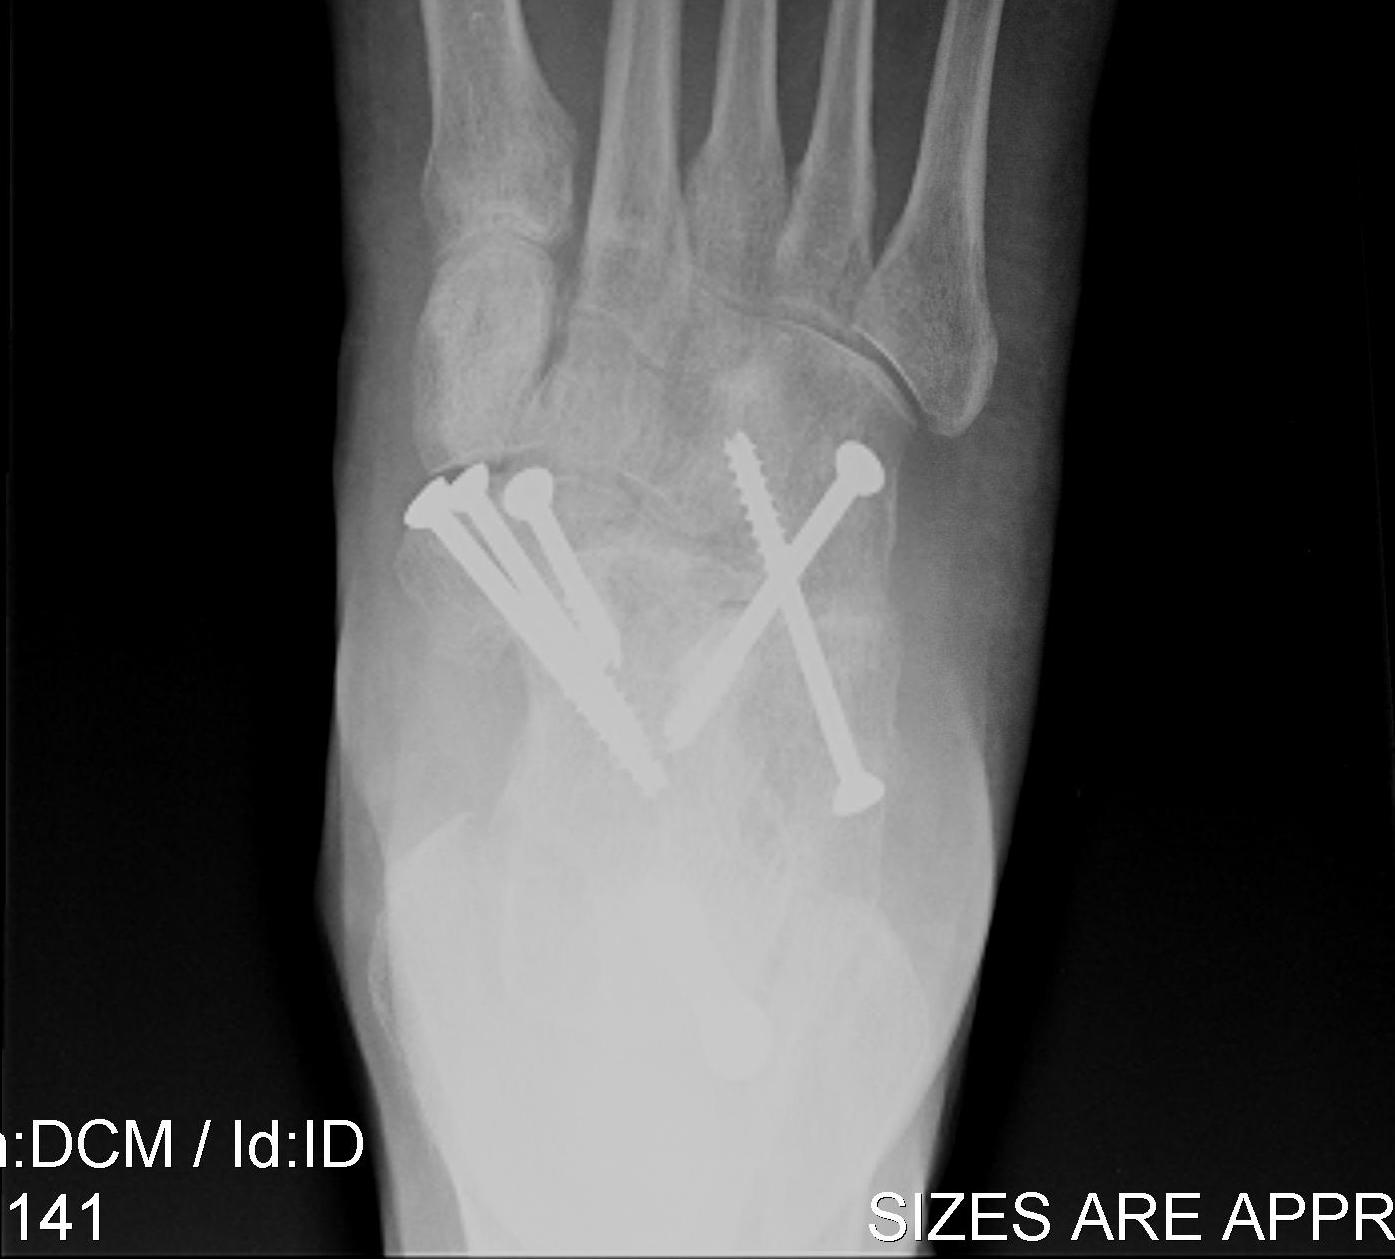

Fixation

- 6.5 mm/ 8.0 mm cannulated screw

- inferior calcaneum into body and neck of talus / talus to calcaneum

- TJN screws

- CCJ screws +/- plate

- STJ screws